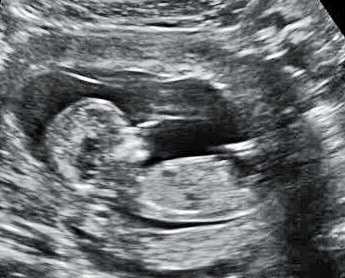

I had a scan today at 13 weeks, and I'm thinking girl but I'm afraid to get my hopes up. Anyone have any input??? TIA

Attachment 23673

Looks girly :)

I agree. Thinking pink!!

Looks girl to me!

Girly!

Pink

girly